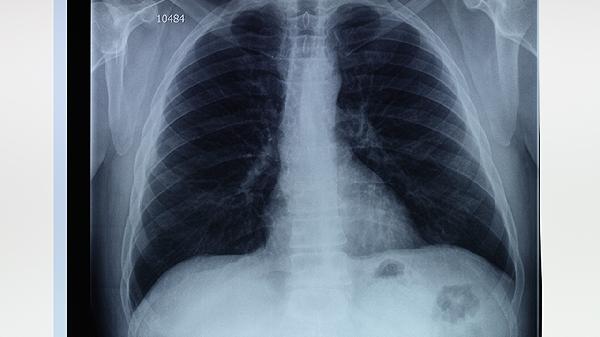

右肺尖鈣化灶通常是指影像學(xué)檢查中發(fā)現(xiàn)的右肺尖部局部鈣鹽沉積,多數(shù)為陳舊性病變或良性表現(xiàn)。鈣化灶可能由肺結(jié)核愈合后遺留、肺部感染恢復(fù)期、塵肺病、錯(cuò)構(gòu)瘤或血管鈣化等原因引起,通常無須特殊治療,但需結(jié)合臨床癥狀與其他檢查綜合評估。

鈣化灶的形成往往與既往肺部損傷修復(fù)過程相關(guān)。當(dāng)肺部組織受到結(jié)核分枝桿菌感染后,機(jī)體免疫系統(tǒng)通過包裹病灶形成肉芽腫,后期鈣鹽逐漸沉積替代壞死組織,最終在X線或CT上呈現(xiàn)高密度影。長期接觸粉塵的職業(yè)人群可能出現(xiàn)肺內(nèi)彌漫性鈣化點(diǎn),與二氧化硅等顆粒誘發(fā)慢性炎癥反應(yīng)有關(guān)。部分良性腫瘤如肺錯(cuò)構(gòu)瘤內(nèi)部可含有軟骨成分,隨生長自然鈣化。老年人血管壁鈣化也可能在影像中表現(xiàn)為孤立性結(jié)節(jié)。

雖然多數(shù)鈣化灶屬于良性改變,但某些特殊情況仍需警惕。當(dāng)鈣化灶伴隨周圍毛刺征、分葉狀輪廓或短期內(nèi)增大時(shí),需排除肺癌合并鈣化的可能。轉(zhuǎn)移性骨肉瘤等惡性腫瘤的肺轉(zhuǎn)移灶偶見鈣化表現(xiàn)。原發(fā)性甲狀旁腺功能亢進(jìn)癥患者因血鈣升高,可能在全身多器官形成異常鈣化灶。對于形態(tài)不規(guī)則或伴隨咳嗽、咯血等癥狀的鈣化灶,建議通過增強(qiáng)CT或PET-CT進(jìn)一步鑒別。

發(fā)現(xiàn)右肺尖鈣化灶后應(yīng)定期隨訪觀察,一般每6-12個(gè)月復(fù)查胸部CT。日常生活中需避免吸煙及二手煙暴露,注意預(yù)防呼吸道感染。從事采礦、建筑等職業(yè)者應(yīng)做好粉塵防護(hù)。若出現(xiàn)持續(xù)胸痛、呼吸困難或體重下降等表現(xiàn),應(yīng)及時(shí)就診呼吸科或胸外科進(jìn)行專科評估。